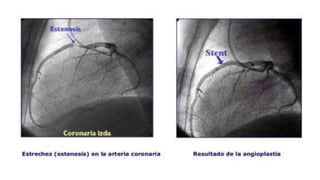

ANGIOPLASTIA CORONARIA

La angioplastia coronaria es el tratamiento de las estrecheces

que se han encontrado durante el cateterismo. Básicamente

consiste en la dilatación de estas estrecheces (estenosis), de las

arterias que riegan el corazón (coronarias). En la mayor parte

de los casos soluciona el problema de las estrecheces de las

arterias del corazón evitando la cirugía.

¿Cómo se realiza?

Por el mismo sitio por donde se está haciendo el cateterismo

(ingle o brazo) llegamos al corazón. Entrando a la arteria hasta la

estrechez y ahí dilatamos hasta arreglarla. Todo este

procedimiento, que a veces es bastante largo, (no es doloroso).

Es normal que note una breve molestia en el pecho cuando

estamos dilatando. Además de dilatar, normalmente también

ponemos un muelle metálico (stent) para mantener dilatada la

zona que estaba estrecha.